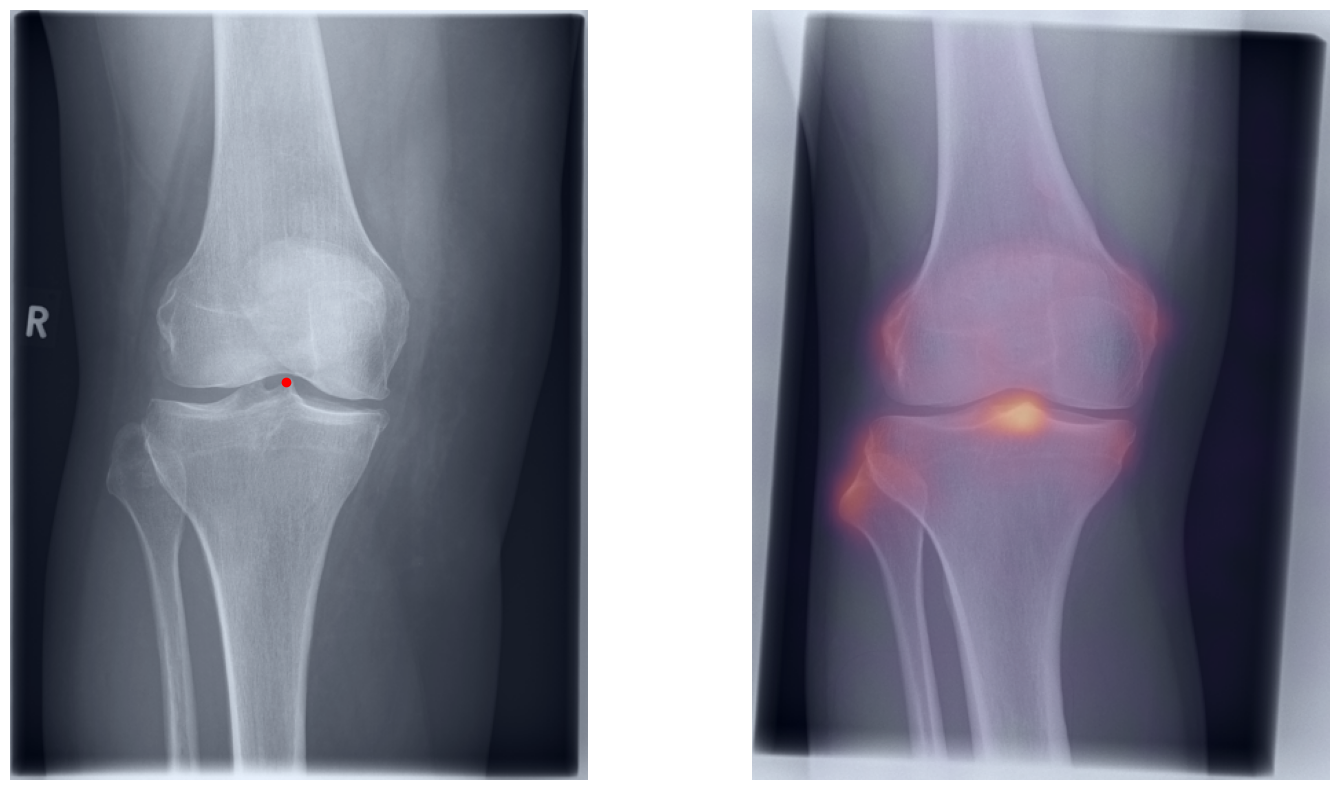

Artificial intelligence (AI) has shown great potential in assisting radiologists with musculoskeletal (MSK) assessments across various anatomical regions1,2,3,4. However, most existing tools are narrowly tailored for specific anatomies or rely on segmentation-based methods as a basis. To address these limitations, we propose a versatile and generalist AI-based approach for landmarks matching. In contrast to typical generalist landmark matching approaches that depend on automatically identified, optimally descriptive landmarks5,6,7, our use-case has to be based on manually selected landmarks tailored for MSK measurements. As these landmarks are potentially subotimal for precise matching, we employ an AI-based method8 that first performs multi-scale dense image matching between the reference and target images independently of the landmarks. The AI uses a combination of transformer and convolutional neural networks to establish a multi-resolution descriptive feature representation of each position within the images, allowing to define correspondences between the reference and target images. In a subsequent step, landmark positions are transferred to the target image based on these correspondences, with the determination of final locations benefiting from the redundancy of the dense matching. This enables robust automation of landmark matching from a reference patient across an entire cohort of target patients. The approach is anatomy-agnostic, enabling the use of the same backbone model for a wide range of anatomical regions and MSK measurements. For more detailed information we refer to our paper.

Once a correspondence between the reference and target radiographs is established, landmark matching can be performed in real-time. This process enables the alignment of individual points and allows for the definition of a predefined set of landmarks that can be mapped onto the target patient. These predefined landmarks can be customized for the automated calculation of specific measurements, which, once defined on a reference patient, can be consistently and automatically transferred to any radiograph within the target cohort.

The process of establishing a dense match between two images relies on abstract feature representations for each position in both the reference and target images. To better understand which information is encoded by the AI, we examined the feature similarities between a specific position within the reference image and the entire target image. Our findings show that the AI captures both semantic and texture features. The matching process utilizes this encoded information, along with precise positional data, to create a reliable mapping between the images.